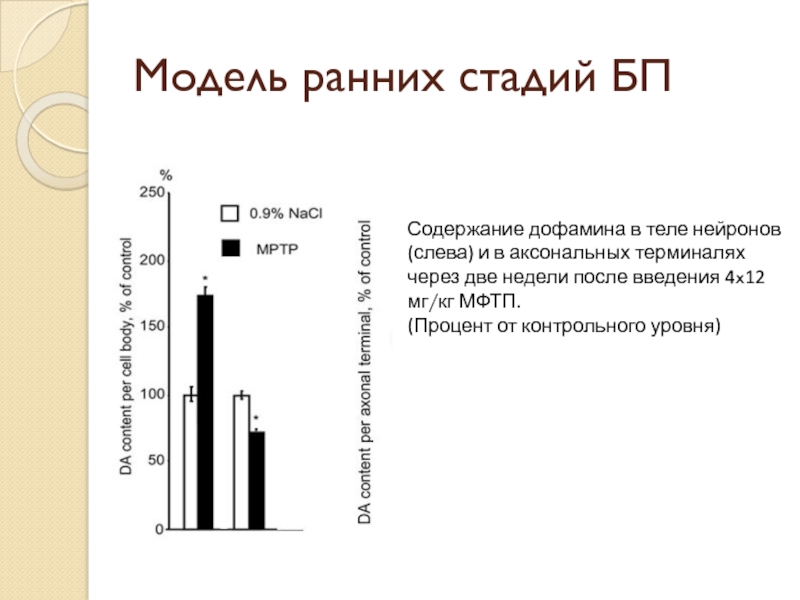

Слайд 7Модель ранних стадий БП

Содержание дофамина в теле нейронов (слева) и

в аксональных терминалях через две недели после введения 4x12 мг/кг МФТП.

(Процент от контрольного уровня)

(Процент от контрольного уровня)